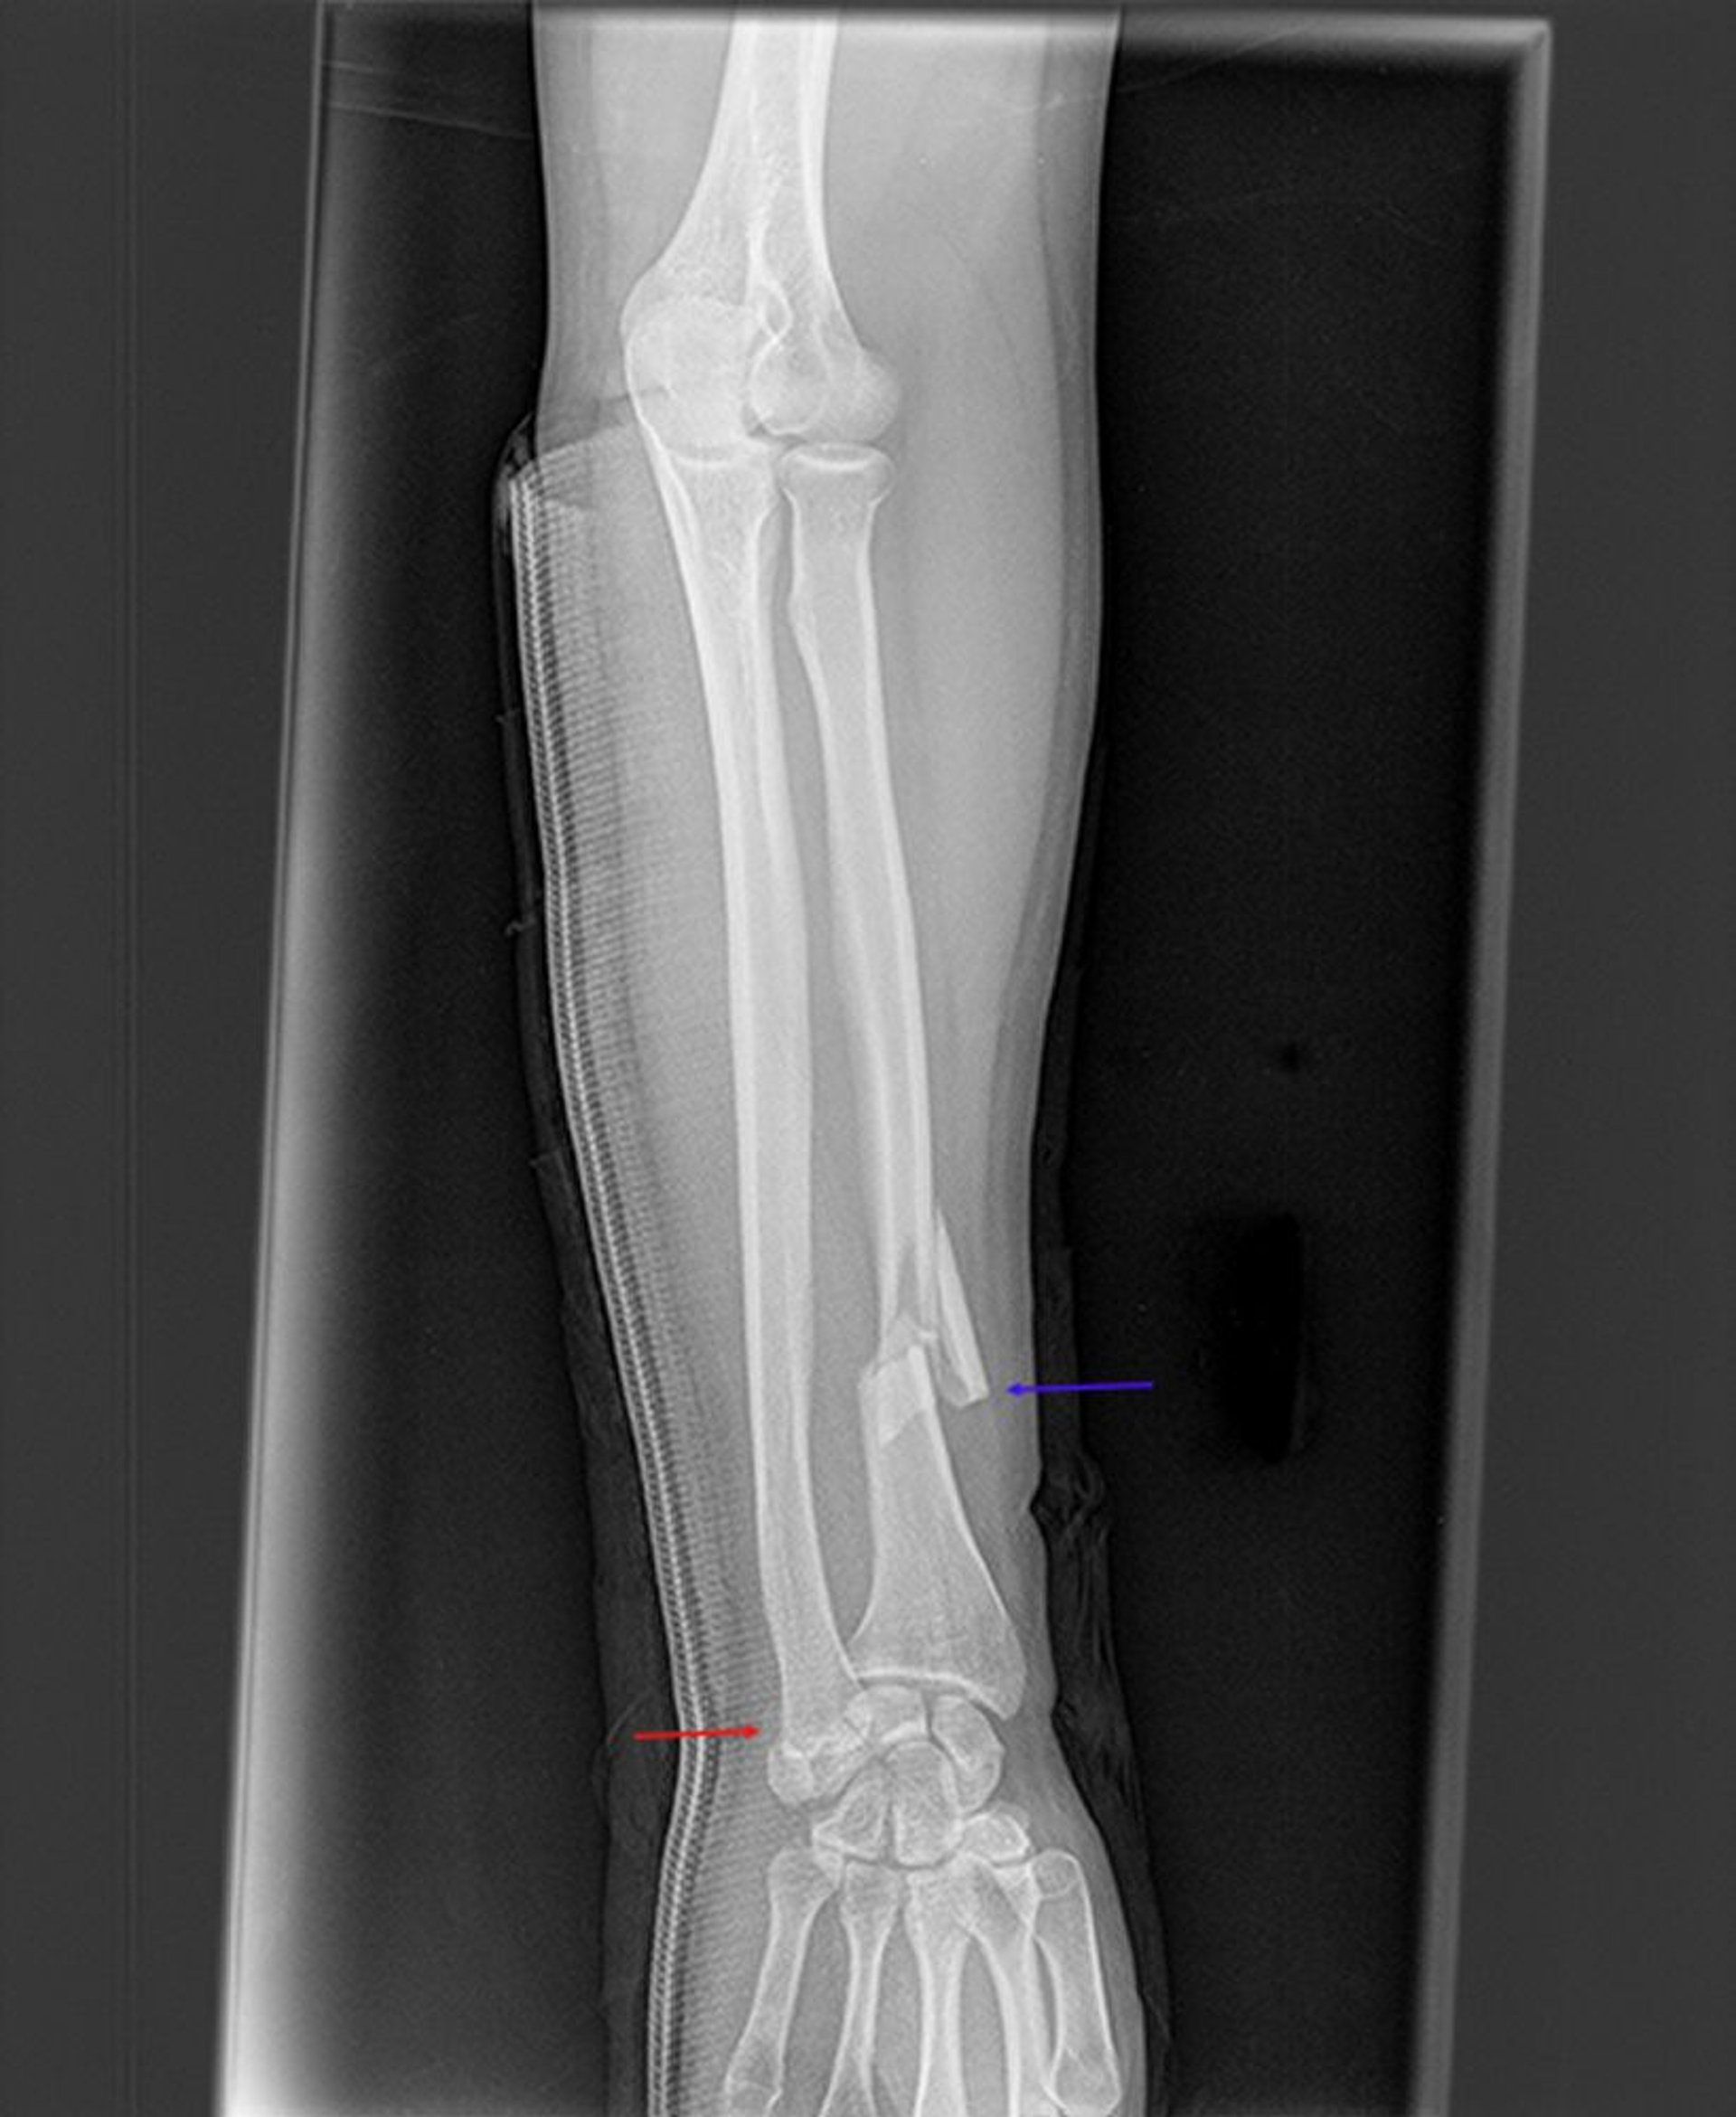

Fractura de Galeazzi

Esta radiografía muestra una fractura del radio distal (flecha azul) y una rotura de la articulación radiocubital distal (flecha roja). Las superficies articulares del cúbito distal y el radio distal no están alineadas entre sí.

Image courtesy of Danielle Campagne, MD.